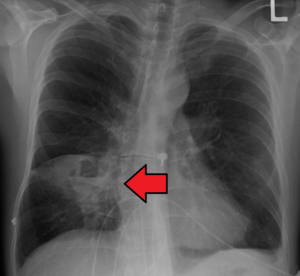

• X-ray (PA Chest):

• Lung abscess can be readily observed as a pus-filled cavity with fluid & air level.

• If the abscess cavity doesn’t contain air, it is difficult to distinguish from a tubercular mass or a tumor mass.

• Lung Abscess on Chest X ray